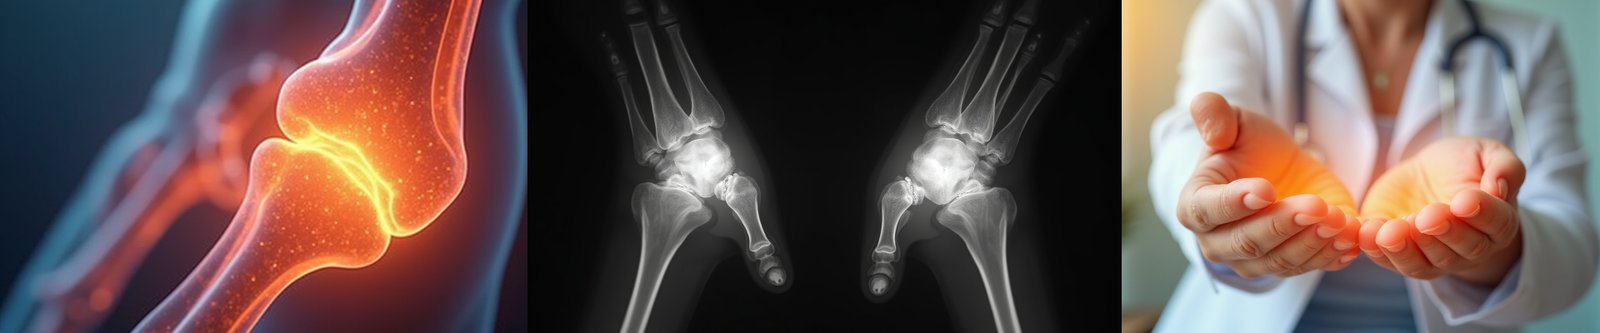

🦴 Joint Pain & Rheumatoid Arthritis

Relieve Pain. Regain Movement. Reclaim Life.

At Ginni Orthopaedic Hospital, we provide specialized care for joint pain and autoimmune conditions like Rheumatoid Arthritis (RA). Our goal is to minimize pain, slow disease progression, and help you regain quality of life with evidence-based care.

πŸ”Ž What is Rheumatoid Arthritis (RA)?

RA is a chronic autoimmune disorder where your immune system attacks the joints, leading to pain, swelling, and deformity if untreated. It typically affects joints symmetrically (e.g., both knees or wrists).

• X-rays for joint damage